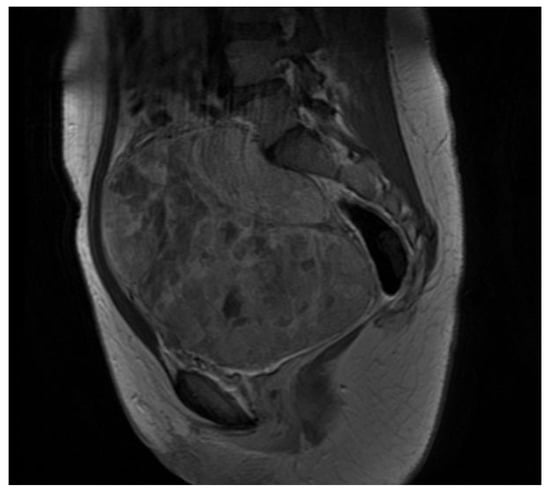

2. Case Presentation